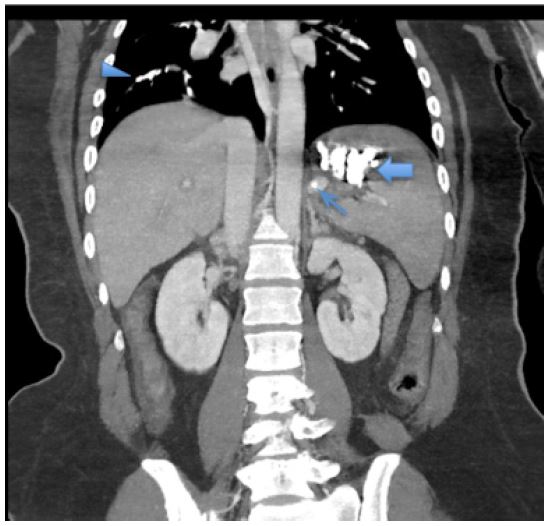

Following the procedure, there was a drop in oxygen saturation and development of tachycardia. The patient was subsequently intubated, ventilated, and transferred to a monitored setting. Thoracic CT angiography revealed bilateral massive non-thrombotic pulmonary embolism with dense infiltrates in pulmonary arterial areas affecting all segmental arterial branches. Embolization material was noted in the splenic vein (Figure 2). Intravenous steroids (dexamethasone 6 mg/day for 2 days, then gradually decrease by 2 mg every 2 days) and supportive management were initiated. Over the next two days, the patient’s oxygen requirements gradually decreased. She was successfully weaned off ventilation, extubated, and discharged home.

Figure 2: Coronal CT scan of the abdomen reveals high-density material in the upper left abdomen, indicating the presence of iodized glue and microcoil embolization of the gastric varix (solid arrows) and splenic vein (arrow). Thoracic images show multiple high-density filling defects in the pulmonary arteries, consistent with non-thrombotic embolization of iodized glue (arrowheads).